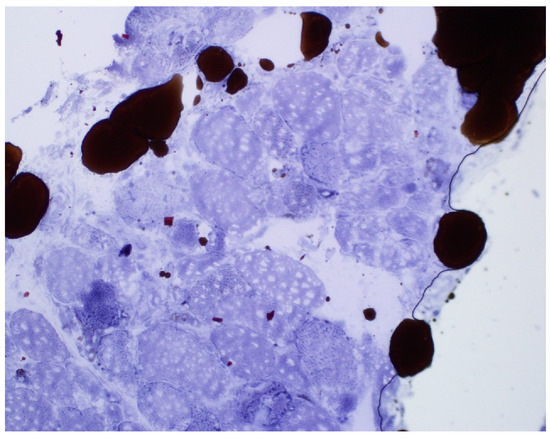

Figure 3.

Sudan black stain: lipid droplets in scattered and intact myofiber (low power).

An 81-year-old woman, with a history of hypertension, dyslipidemia, T12 compression fracture and Alzheimer’s dementia, presented to established care at a geriatric clinic with a chief complaint of two months of gradual progressive symmetric proximal muscle weakness. At baseline, the patient was functionally dependent only on her instrumental activities of daily living. However, her severe weakness resulted in new functional deficits including difficulties in standing, walking and transferring. On medication reconciliation, the patient was noted to be taking atorvastatin 40 mg from two different bottles, doubling her daily dose. Atorvastatin had been started for primary prevention at the age of 79 for an atherosclerotic cardiovascular disease (ASCVD) risk score of >7%. Additional medications at the time of her clinic visit included amlodipine 5 mg daily, donepezil 5 mg nightly, memantine 10 mg twice a day, pantoprazole 40 mg a day and a calcium/Vitamin D supplement. Her exam was significant for 3/5 strength in hip flexors, resulting in the inability to stand unassisted and an inability to abduct her arms past 90 degrees. She was started on prednisone 15 mg orally a day for a presumed diagnosis of polymyalgia rheumatica, and her statin was discontinued. Two weeks later, she was seen in follow-up in the geriatric clinic and found to have profound weakness in the upper and lower extremities as well as new dysphagia and mild dysarthria. She was admitted to the hospital where her workup was notable for mildly elevated troponin-I, elevated AST and ALT and a creatine kinase (CK) of 7630 U/L (normal 38–234 U/L). A urine dipstick showed 3 + blood with only one RBC/high powered field on microscopy. Creatinine was within normal limits. Electromyography (EMG) showed a proximal greater than distal irritable myopathy. A muscle biopsy of the left quadriceps showed segmental necrosis of skeletal muscle fascicles with perivascular infiltration by T-cells, B-cells and plasma cells, and lipid droplet accumulation was consistent with an immune-mediated necrotizing myopathy causing rhabdomyolysis (Figure 1, Figure 2, Figure 3 and Figure 4). Anti-HMG CoA reductase antibodies were positive at >200 units (normal <20 units), whereas ANA, anti-Jo, MI-2, SRP, RNP, Smith, Scl-70 and SS-A/SS-B antibodies all were negative.

The differential for the progressive weakness of proximal muscles in an elderly patient includes both PMR and myopathies. Myopathies can usually be readily differentiated from PMR in that CK is generally elevated. Patients with PMR should not have objective weakness; rather, they typically present with pain limiting their movements [4,5]. In this case, the acute onset and rapid decline of proximal muscle strength in the setting of a markedly elevated CK was most consistent with myopathy. Ultimately, the final diagnosis of statin-induced immune-mediated necrotizing myopathy was cinched by the markedly elevated anti-HMG CoA reductase antibody in combination with characteristic findings on muscle biopsy. Anti-HMG CoA reductase antibodies can be present in the absence of a statin exposure; however, most cases are associated with statin use, particularly those observed in older patients. While the risk of myotoxic side effects of statins have typically been associated with higher potency statins, a dose–response relationship with respect to statin-induced immune-medicated necrotizing myopathy has not been well established [6].